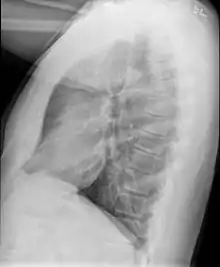

Causes include breathing in toxic fumes, respiratory infections, connective tissue disorder or complications following a bone marrow or heart-lung transplant.[1] Symptoms may not occur until two to eight weeks following toxic exposure or infection.[1] The underlying mechanism involves inflammation that results in scar tissue formation.[1] Diagnosis is by CT scan, pulmonary function tests or lung biopsy.[1] A chest X-ray is often normal.[4]

Medical imaging

Early in the disease chest radiography is typically normal but may show hyperinflation.[6] As the disease progresses a reticular pattern with thickening of airway walls may be present.[4][6] HRCT can also show air trapping when the person being scanned breathes out completely; it can also show thickening in the airway and haziness in the lungs.[11] A common finding on HRCT is patchy areas of decreased lung density, signifying reduced vascular caliber and air trapping. This pattern is often described as a "mosaic pattern", and may indicate bronchiolitis obliterans.[6]